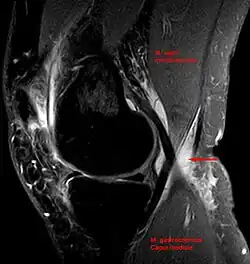

Diagnosis is by examination. A Baker's cyst is easier to see from behind with the patient standing with knees fully extended. It is most easily palpated (felt) with the knee partially flexed. Diagnosis is confirmed by ultrasonography, although if needed and there is no suspicion of a popliteal artery aneurysm then aspiration of synovial fluid from the cyst may be undertaken with care. An MRI image can reveal presence of a Baker's cyst.